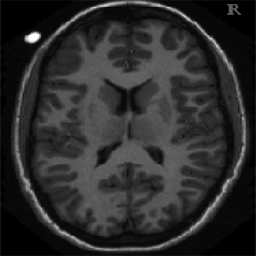

4.1. Uniform Gaussian noise

In this first experiment, we consider the denoising problem with brain scan images. The first set consists of images of pixels and Gaussian noise with zero mean and variance . The original and noisy images are shown in Figure 4.1. The domain decomposition-semismooth Newton algorithms run with the parameter values , , and . The results are shown in Figure 4.2. From the surface representation of , we can observe that is continuous and its shape is related to the one of the original image. In particular, the regularization is stronger in homogeneous regions in the image, and weaker where the image intensity undergoes variations on a smaller scale.